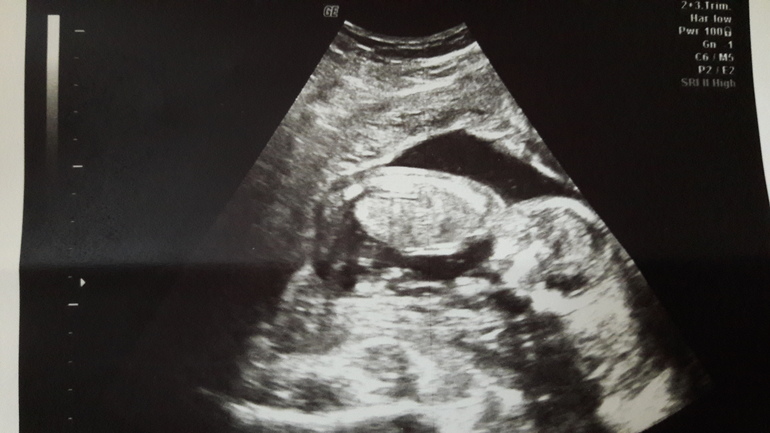

Пол малышаПо м. вчера у меня было 15+4...Шла к уже проверенной УЗИ стке.... Легла в общем, всё хорошо! Всё на месте и всё со мною!!!! Сердечко бьётся, лялечка на месте))))

Прикреплены по задней с тенке, с плацентой всё гуд! 135грамм моя кровинка. Ножки, ручки, головка, сердечко....

Повернула экран и показывала мне мою дочь. Она там брыкалась, отвернулась)))) Так смешно следить за ними... И так быстро забывается увиденное!!!!! Самое главное, что девочка растёт) Это так приятно осозновать!!!!! Мууууурррр!!!!!! ![]()

Ножки.... И потом показала писечку... Доченькино зернышко!!!

Да и долго она мне её показывала.... Потом говорит, не хочет она поворачиваться))))) Хотела лицо показать)))) 😊Не захотеееела!) Вредина моя, ещё одна))))) Короче, я довольна!!!! И уже не жду что тонибудь там вырастет))) Довольна тем что я стану мамой для ещё одной девочки.... Это же баааанда!!!!! ![]()